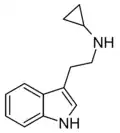

| NcPT | artificial | H | H | C3H5 | N-cyclopropyltryptamine | |